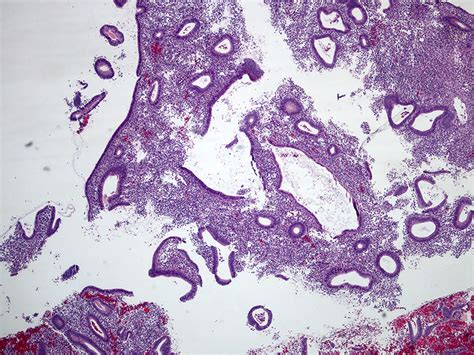

Weakly Proliferative Endometrium refers to a condition where the endometrium does not thicken adequately during the proliferative phase of the menstrual cycle. The proliferative phase is the first half of the menstrual cycle, during which the endometrium prepares for potential implantation of a fertilized egg. In a normal cycle, the endometrium thickens under the influence of estrogen. However, in cases of Weakly Proliferative Endometrium, this thickening is insufficient, which can impact fertility and overall reproductive health.

• Endometrial Biopsy: A small sample of the endometrium is taken for laboratory analysis to evaluate its structure and function.